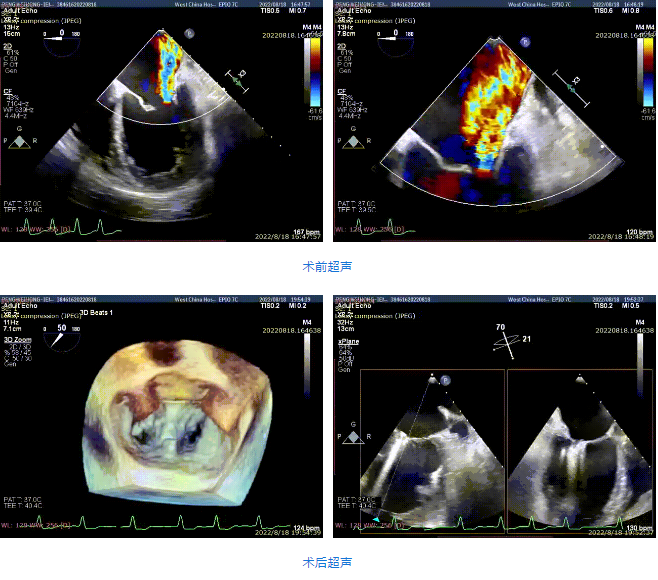

接受治療的是一例59歲男性患者,主訴“心累氣促5余年,加重伴胸痛1個多月”,已經(jīng)過規(guī)范化藥物治療。術(shù)前超聲提示左心明顯增大,右心稍大。左室心尖部肌小梁增多。室間隔及左室后壁厚度正常,左室后下壁基底段變薄、稍向外膨出,搏幅明顯減弱,余室壁搏幅減低,左室壁整體運(yùn)動欠協(xié)調(diào)。二尖瓣瓣尖稍增厚,回聲稍增強(qiáng),后瓣受牽拉,活動度差,前瓣關(guān)閉錯位,開放尚可。多普勒提示:二尖瓣大量反流(VC=6*18mm,EOA=0.53cm2,Vol=61ml);二尖瓣環(huán)舒張期運(yùn)動頻譜呈單峰,EF=30%。

手術(shù)采用全身麻醉插管,經(jīng)股靜脈-房間隔入路,在TEE和DSA引導(dǎo)下完成房間隔穿刺。置入瓣膜夾系統(tǒng)后,在左房調(diào)整瓣膜夾的位置和軸向,后進(jìn)入左室,在TEE引導(dǎo)下捕捉二尖瓣前后瓣葉,并關(guān)閉瓣膜夾。經(jīng)TEE反復(fù)確認(rèn)手術(shù)效果后最終鎖定并釋放瓣膜夾。術(shù)后即刻超聲顯示瓣膜夾位置穩(wěn)定,功能良好,肺靜脈逆流和左房壓都明顯好轉(zhuǎn)。